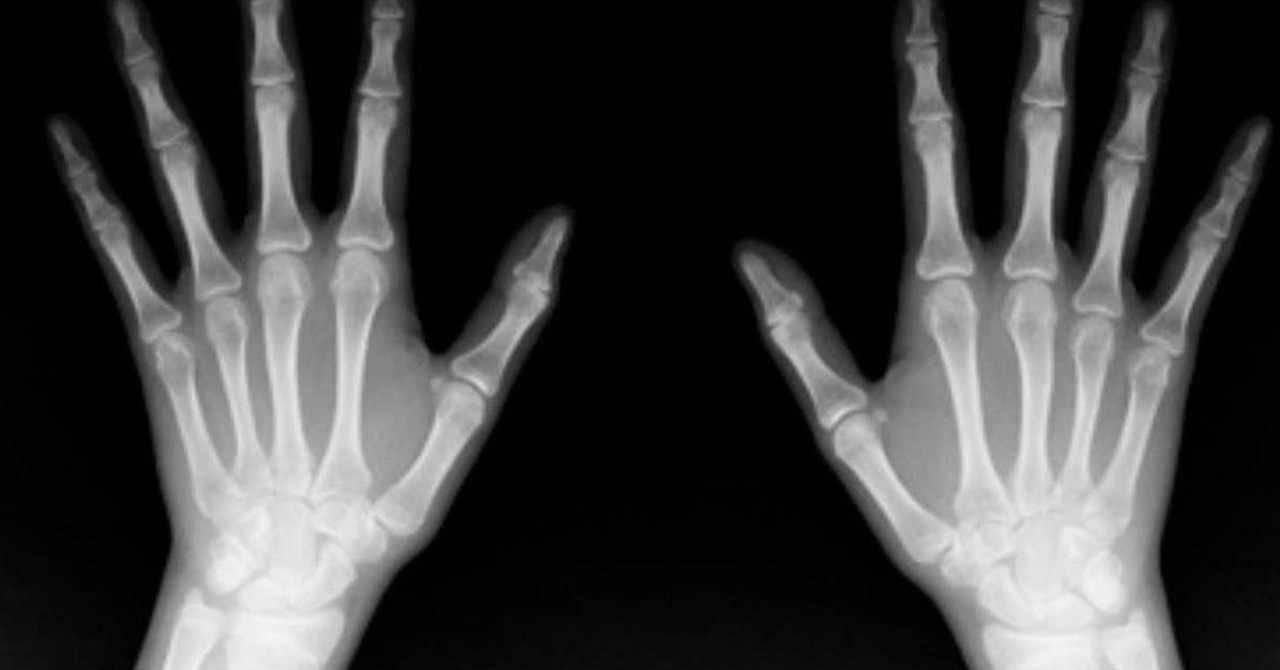

X線不透過像はどう読む 日経メディカル

X線 レントゲン 写真に写るもの 写らないもの Ashley アシュレイ